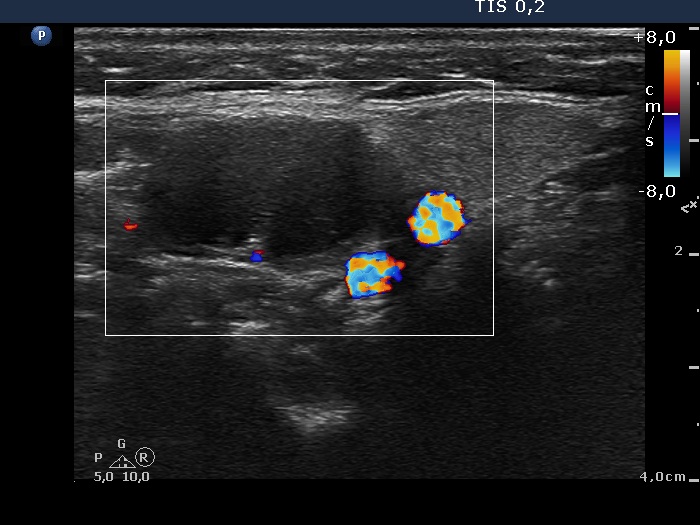

Ultrasonography. The right thyroid was moderately hypoechogenic without any circumscribed lesions. The left thyroid was removed. There were several enlarged lymph nodes in the right submandibular area. The largest one presented two discrete, more hypoechogenic intranodal lesions and a regular hilum.

Comment. This is an unusual case, the nodes (particularly those presented in the video) seem to be benign, reactive-type ones.